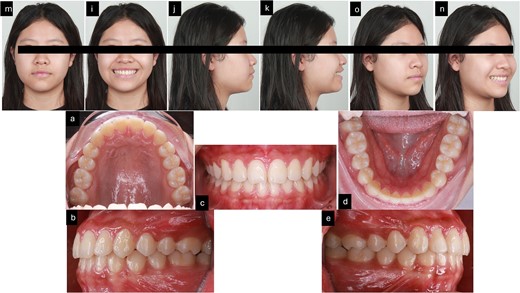

After 16 months of orthodontic treatment, all treatment objectives were successfully accomplished. This resulted in a well-aligned dentition with all spaces closed, leading to enhanced facial aesthetics, and retracted upper incisors. The overbite and overjet were within normal ranges, achieving a Class I occlusion. There was also a visibly reduced GS after treatment. The superimposition and cephalometric analysis table before and after treatment showed significant improvements in profile and incisor inclination, the clear aligner removable appliance was used for retention (Figs 5 and 6, and Table 1). After 2 weeks of periodontal surgery, the patient’s gingival line has healed exceptionally well. It now wraps around the tooth roots in a scalloped shape, with no black triangles or exposed tooth roots. The surgery also fixed the patient’s GS, resulting in an ideal gingival exposure. As a result, the crowns of the teeth are more visible and stable up to 3 months (Fig. 7).

Post-treatment records. (a–f) Extra oral pictures post-treatment; (g–t) post-treatment radiographies; o: superimposition before and after treatment; (i–n) intraoral pictures post-treatment.